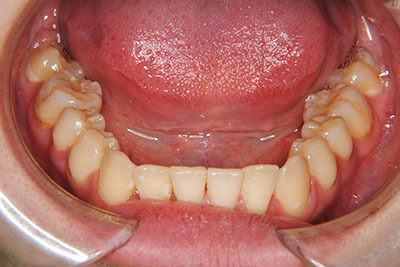

お口の中を診ますと、左上第二小臼歯が歯列の内側に生え、左上犬歯のスペースは全くない八重歯となっていました。検査結果から骨格的な不正はなく。上奥歯が前にずれたかみ合わせで前歯は合っていて出っ歯ではないので左右1本ずつ歯列からはみ出した状態であることがわかりました。上の奥歯を横の歯1本分後ろにずらすことは困難なので、右上中側に生えている第二小臼歯と八重歯である左上犬歯の次の歯=第一小臼歯の2本を抜歯し治療しました。

マルチブラケット装置(T21ブラケット)に加えて口の中のゴムをたいへん頑張って使っていただいた結果、治療前の予想期間1年から1年半であったところ、10カ月で動的治療を終了できました。上下真ん中のズレも治りぴったりになりました。 これからは歯並びの維持安定のためリテーナー(保定装置)を使いながら定期健診となります。